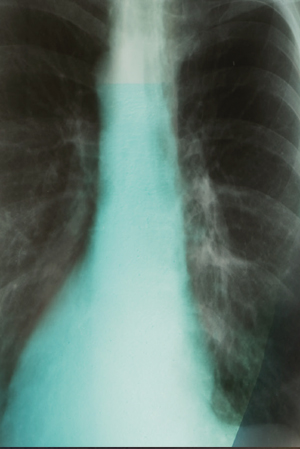

Low Dose CT Scan for Lung Cancer Screening

Fox Chase Cancer Center (FCCC) is one of the country’s leading cancer research and clinical organizations with a history of over 100 years in cancer treatment and research. FCCC engaged Fox Management Consulting to assess the market and the available offerings for low dose CT scan lung cancer screening. FCCC was provided with a comprehensive marketing plan, detailed financial model, and opportunities for grant funding. Read more.